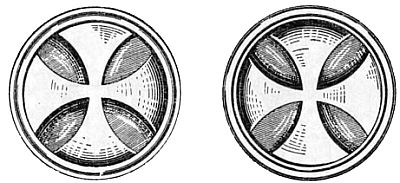

Глаза, совершенно свободные от этого недостатка, у людей встречаются редко, в чем легко можно убедиться, рассматривая приведенные здесь рис. 7, 8 и 9.

Рис. 7. Концентрические, близкие друг к другу окружности кажутся, прерванными, не одинаково удаленными друг от друга.

Рис. 8. Одинаковая (однотонная) штриховка квадрантов этого круга кажется не одинаково яркой.

Рис. 9. Те или иные буквы кажутся более темными в зависимости от положения рисунка относительно глаза.

Для испытания глаз на астигматизм врачи-окулисты часто применяют специальную таблицу (рис. 10), где двенадцать кружков имеют штриховку равной толщины через одинаковые интервалы.

Рис. 10. Фигура для определения степени и меры астигматизма глаза.

Глаз, обладающий астигматизмом, увидит линии одного или нескольких кружков более черными. Направление этих более черных линий позволяет сделать вывод о характере астигматизма глаза.

Если астигматизм обусловлен несферической формой поверхности хрусталика, то при переходе от ясного видения предметов горизонтальной протяженности к рассматриванию вертикальных предметов человек должен изменить аккомодацию глаз.

Чаще всего расстояние ясного видения вертикальных предметов меньше, чем горизонтальных. Это частично связано со зрительным дефектом «переоценки вертикальных линий», о чем будет сказано далее (см. п. 5).